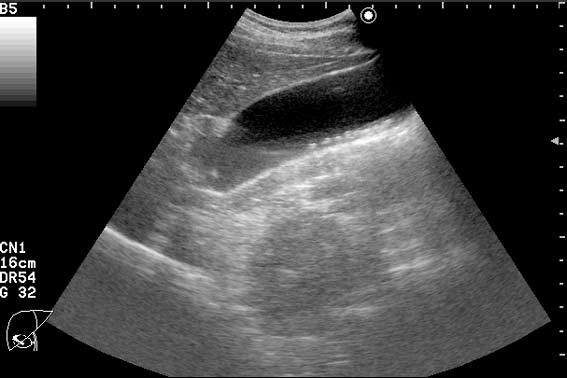

Пациент с приступом резких болей в животе, тошнотой, рвотой.

может это сладж?

"Горошек" в пузыре и холедохе.

Да, ЖКБ, ходедохолитиаз, холецистолитиаз